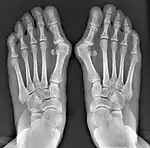

Normal foot skeleton

Fig 1a: Normal foot skeleton

First metatarsal bone has moved aside

Fig. 1b: First metatarsal bone has moved aside

Primus varus deformity

Primus varus deformity is the leaning of the first metatarsal bone away from the second metatarsal and towards the opposite foot (Fig. 1). As it leans over, its head sticks out to form the bunion bump and it also widens the forefoot to cause shoes feeling too tight. Thus when bunion pain becomes unmanageable, surgical correction is to narrow the forefoot by repositioning of the first metatarsal head back to its normal position. This can be done by osteotomy (bone-breaking), soft tissue (non-osteotomy) or fusion techniques.